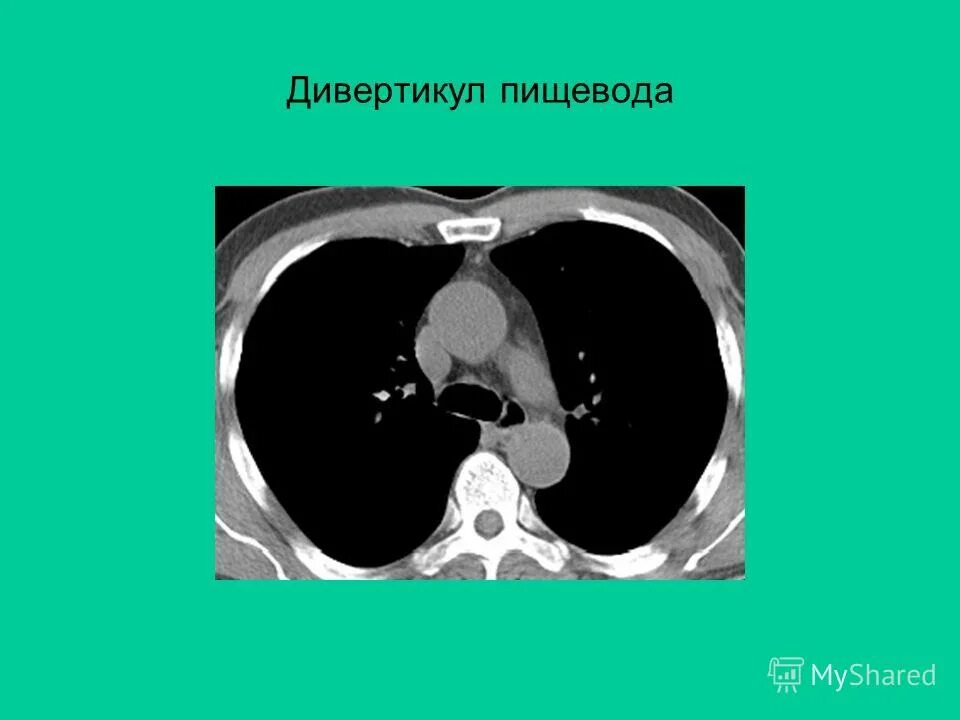

Н 3 кт